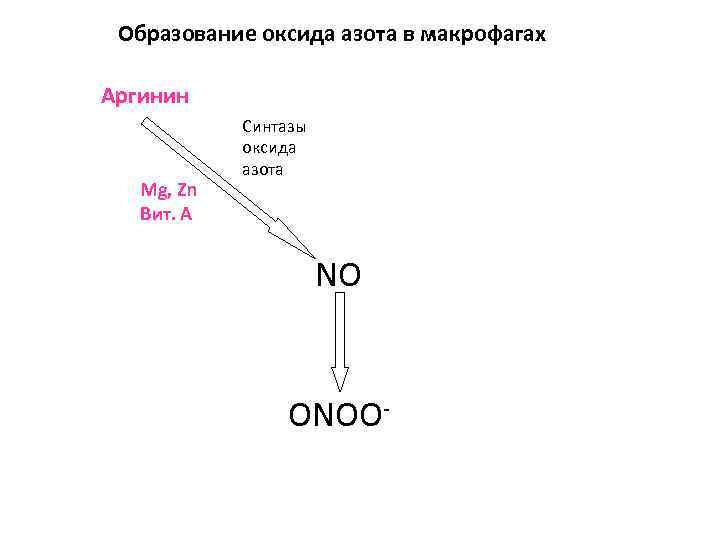

Ключевой эндогенный свободнорадикальный продукт, разрушающий гельминтов в организме млекопитающих, - пероксинитрит -!!! ONOO 13

ONOO-!!! NO ONOO 14

Исходным соединением для образования пероксинитрита служит оксид азота (NO) NO представляет собой универсальный внутриклеточный медиатор, играющий важную роль в: • регуляции сосудистого тонуса • регуляции функции тромбоцитов • прилипании лейкоцитов к клеткам-мишеням • регуляции размножения гладкомышечных клеток • передаче нервных импульсов • противоинфекционном иммунитете

Образование оксида азота в макрофагах Аргинин Mg, Zn Вит. А Синтазы оксида азота NO ONOO-